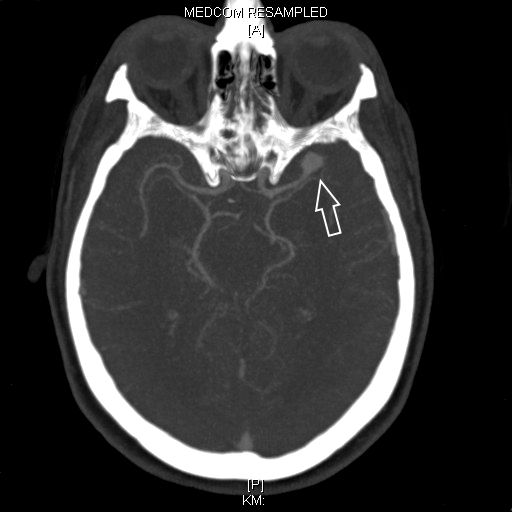

Als schnellste und sicherste Maßnahme gilt das craniale Computertomogramm (CCT). Hier lässt sich eine frische SAB meist zuverlässig darstellen, wobei auch bereits richtungsweisende Befunde, wie das Ausmaß der Blutung und eine eventuelle Lokalisation eines möglichen Aneurysmas bestimmt werden können. Darüber hinaus kann ein Angio-CCT, bei dem zusätzlich Kontrastmittel verabreicht wird und dann die intrazerebralen Blutgefäße gesondert rekonstruiert und dargestellt werden, weitere Informationen liefern. Der sogenannte “Goldstandard” zur Diagnose zerebraler Gefäßmissbildungen ist jedoch die zerebrale Angiographie. Dabei wird mit Hilfe eines speziellen Katheters über die Leisten- oder Armarterie Kontrastmittel gegeben und die zerebralen Blutgefäße hoch selektiv dargestellt. Sollten sich auf dem initialen CCT Zeichen des Hirnwasseraufstaus zeigen, der durch ein Verstopfen der Abflusskanäle durch das neu aufgetretene Blut bedingt ist, ist oft die Anlage einer Hirnwasserableitung nach außen notwendig (externe Ventrikeldrainage).

CT Bildgebung der klassischen subarachnoidalen Blutverteilung nach SAB

3D Darstellung eines Aneurysmas

CT-Angiographie eines gebluteten Aneurysmas